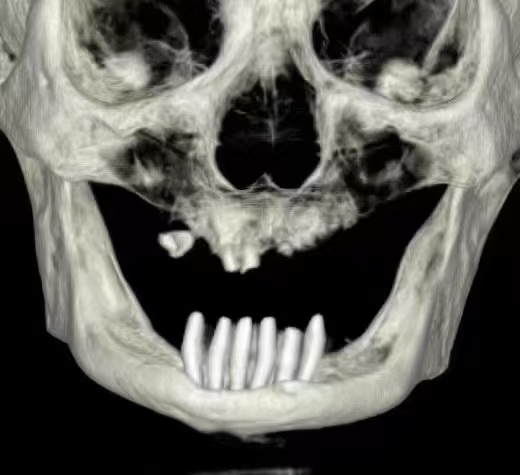

严重的种植并发症一例

严重的种植并发症

触目惊心